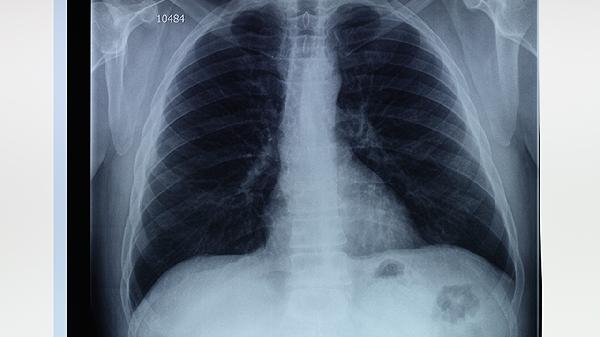

肺氣腫、肺大泡合并肺動脈高壓屬于較嚴(yán)重的呼吸系統(tǒng)疾病組合,其嚴(yán)重程度主要與肺功能損害程度、并發(fā)癥風(fēng)險及肺動脈壓力水平相關(guān)。病情發(fā)展可能影響氣體交換效率,增加右心負(fù)荷,甚至導(dǎo)致呼吸衰竭或肺源性心臟病。

肺氣腫導(dǎo)致肺泡壁破壞,肺大泡形成后進(jìn)一步減少有效呼吸面積,二者協(xié)同作用會顯著降低肺的彌散功能和通氣效率?;颊叱1憩F(xiàn)為活動后氣促、血氧飽和度下降,嚴(yán)重時靜息狀態(tài)下也會出現(xiàn)呼吸困難。

長期缺氧引發(fā)肺血管收縮和重塑,使肺動脈平均壓持續(xù)≥25mmHg。這會加重右心室后負(fù)荷,初期表現(xiàn)為代償性心室肥厚,后期可能出現(xiàn)右心衰竭,伴隨頸靜脈怒張、下肢水腫等體循環(huán)淤血體征。